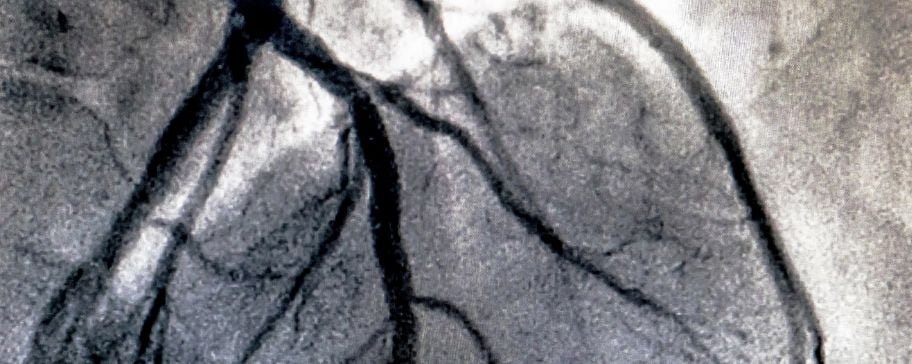

La angiografía pulmonar es una técnica que complementa al cateterismo cardiaco derecho. Tras la inyección de un medio de contraste en el sistema circulatorio pulmonar, se obtienen imágenes mediante rayos X que permiten visualizar las arterias de ambos pulmones. Con esta técnica es posible identificar obstrucciones o estrecheces, su localización exacta, cuántas arterias están afectadas y la severidad de las lesiones (estrechamientos).